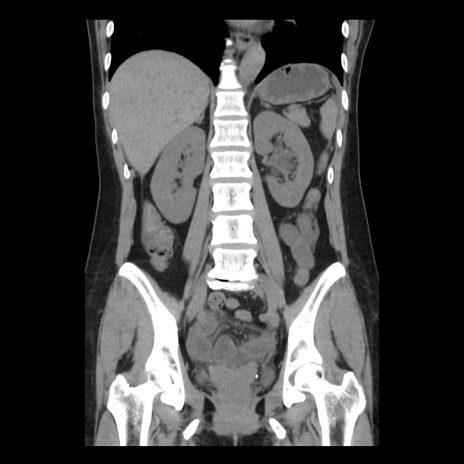

症例10(冠状断像)

【症例】 50歳代女性

【主訴】 腹痛

【現病歴】前日生レバーを食べた。今朝に排便あり。 昼前に突然発症の腹痛を生じ、当院救急外来を受診した。

【既往歴】 子宮筋腫にてで子宮全摘後

【身体所見】 意識清明、腹部:平坦、軟、下腹部やや左を中心に圧痛・反跳痛あり、筋性防御あり

【データ】WBC 7800、CRP 0.07